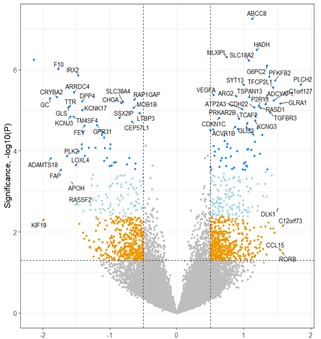

The left image is the GeoMx DSP instrument, the middle image is a sample of regions of interest, or ROIs, in a biological sample that have been selected by a researcher using GeoMx DSP for further analysis, and the right image is a “volcano plot” comparing the differential gene expression across regions within the biological sample.

The primary technologies historically used by researchers and clinicians to analyze gene activity in selected parts of a biological sample include immunohistochemistry, or IHC, which is used to estimate amounts of protein, and in-situ hybridization, or ISH, which is used to estimate amounts of RNA. Both IHC and ISH use fluorescent stains that provide the ability to identify typically four proteins or RNA at a time based on assigned colors. The colors aid researchers in identifying where certain proteins or RNA may reside in a sample and provide a visual approximation of amounts. These techniques are generally limited however in their ability to only look at four proteins or RNA at a time and offer no ability to precisely quantify the amounts present in any given region or cell type. These limitations may lead to incomplete scientific conclusions as to the most relevant biological pathways in any given sample.

GeoMx DSP is designed to allow researchers to quantify a much larger number of RNA or proteins spatially within multiple regions of interest across the landscape of a heterogeneous section of a biological sample. Our GeoMx DSP instrument images slide-mounted or freshly cut sample sections, allowing users to select regions of interest for subsequent quantification and analysis, or molecular profiling. The post-selection profiling or “read out,” can be performed using either our nCounter Analysis System, or an Illumina NGS system.

We believe GeoMx DSP offers a number of advantages as compared to traditional spatial technologies, including the ability to profile both RNA and protein, the ability to multiplex large numbers of different RNA or proteins simultaneously in each selected region, flexibility on the selection of regions to analyze, and the ability to process 10 or more biological samples per day.